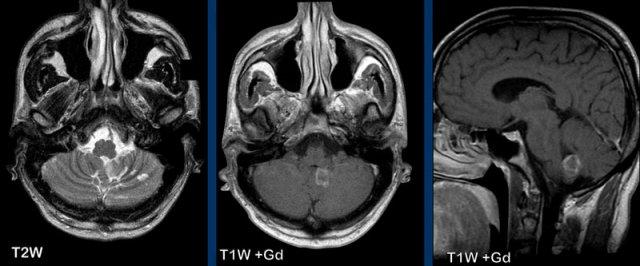

Các hình ảnh này của một trẻ 9 tuổi nhập viện vì đau đầu.

Hình ảnh

Có một khối nang lớn ở hố sau gây chèn ép và tắc nghẽn não thất bốn và thân não.

Ghi nhận một nốt đặc ngấm thuốc tương phản, cùng với sự ngấm thuốc của thành nang.

Kết luận

Chẩn đoán có khả năng nhất ở độ tuổi này là u nguyên bào thần kinh đệm lông.

U nguyên bào mạch máu (Hemangioblastoma)

U nguyên bào mạch máu thường gặp nhất ở tiểu não, nơi đây nó là u tân sinh nguyên phát thường gặp nhất ở người lớn.

Ít gặp hơn ở tủy sống.

Khối u bắt đầu là một nốt đặc và dần dần hình thành nang.

Nốt nằm ở phía màng mềm (phần trong của màng não).

Thành nang không phải là một phần của khối u và thông thường không ngấm thuốc, trừ trường hợp có chảy máu trong nang.

Do thành nang không phải là mô u, nên không cần thiết phải cắt bỏ toàn bộ nang.

Các hình ảnh này của một phụ nữ 63 tuổi mắc bệnh von Hippel-Lindau.

Hãy quan sát kỹ. Dấu hiệu nào khó nhận thấy?

Có một nang lớn với một nốt nhỏ ngấm thuốc ở bán cầu tiểu não phải.

Thành nang không ngấm thuốc.

Lưu ý nốt u nằm ở phía màng mềm (mũi tên).

Có thêm hai nốt nhỏ ngấm thuốc ở mặt sau của tiểu não.

Đa u hầu như luôn liên quan đến bệnh von Hippel-Lindau.